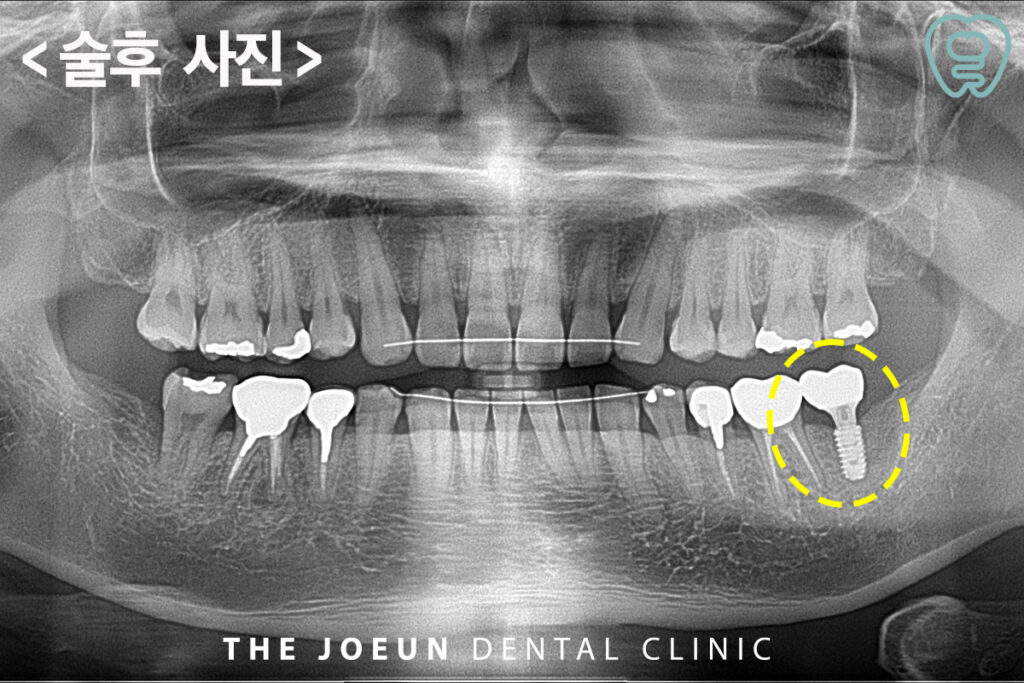

최종 보철 후의 사진입니다.

치조골이 충분하지 않으면 임플란트가 흔들리거나 골융합이 제대로 이루어지지 않아 전체 치료가 실패할 가능성이 커지는데요. 환자마다 치조골 손실 양상과 회복 속도가 다른 만큼 정밀 진단 후 필요한 범위의 뼈이식을 진행하고 이후 회복 단계에서의 관리가 철저해야 만족스러운 결과를 얻을 수 있습니다.